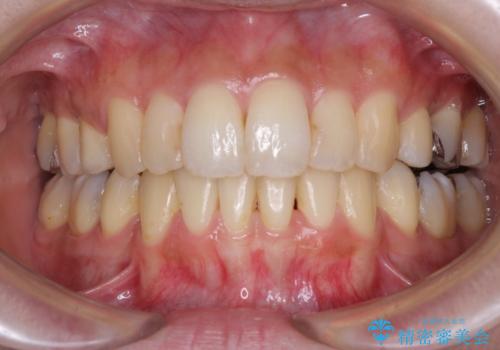

矯正治療の後戻り ガタガタになった前歯の部分矯正

もう少しデコボコを改善したかったのですが、ご本人の希望もあり、装置を除去しました。

後戻りを防止するため、舌側を細いワイヤーによる保定を行いました。